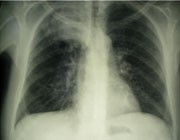

Abb. 1: Großes Bronchialkarzinom rechter Oberlappen

Non-ADM finden sich bei HIV-Patienten inzwischen mindestens so häufig wie die beiden wichtigsten ADM, nämlich maligne Lymphome und das Kaposi-Sarkom. Non-ADM sind folglich auch ein signifikanter Mortalitätsfaktor und führen inzwischen zu mehr Todesfällen bei HIV-Patienten als die ADM. In den meisten Kohortenstudien liegt der Anteil maligner Erkrankungen an allen Todesfällen bei HIV-infizierten Patienten bei 15-25%. Maligne Erkrankungen tragen damit mehr zur Mortalität bei als zum Beispiel eine chronische Hepatitis C oder kardiovaskuläre Erkrankung.